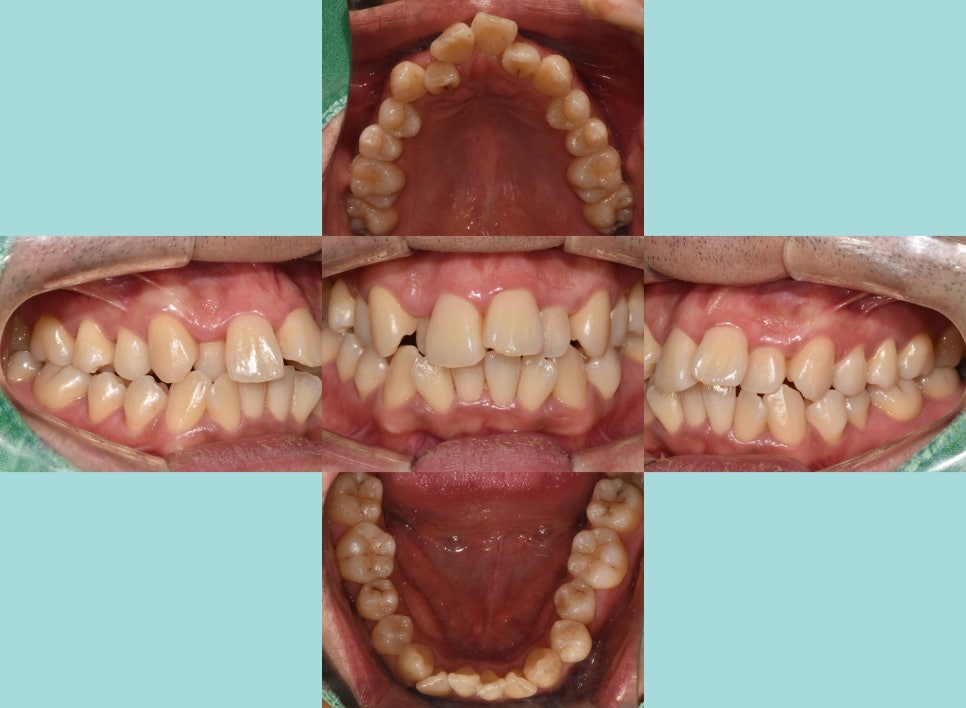

좀 더 자세히 내부를 들여다봤을 때,

되게 어지럽게 배열되어있는 모습을 볼 수 있습니다.

특히나 전치부에 집중된 총생(crowding)은

배열을 들쑥날쑥하게 만듭니다.

사진에서 보여지듯이 12번은

반대교합의 형태도 나타내고 있었는데요.

다른 곳들은 윗니가 아랫니를 덮는 반면에

오른쪽 아랫니 송곳니 부분이 위쪽의 12번을

덮고 있는 형태로 반대교합을 보여줍니다.

이러한 총생은 이가 올바르게 자리 잡지 못하고

겹치거나 삐뚤어지게 나온 상태를 말합니다.

오래 방치할수록 턱뼈의 크기와 치아 크기의 불균형을

만드는 원인이 됩니다.

이렇게 좁은 공간 안에서

이들이 비정상적으로 배열되는 것이 특징이며,

주로 전치부에 자주 나타납니다.

맹출 할 공간의 부족으로 인해 총생이 생겨나면서

이로 인해 앞니 뻐드렁니도 자연스럽게

만들어져 돌출된 느낌을 줍니다.